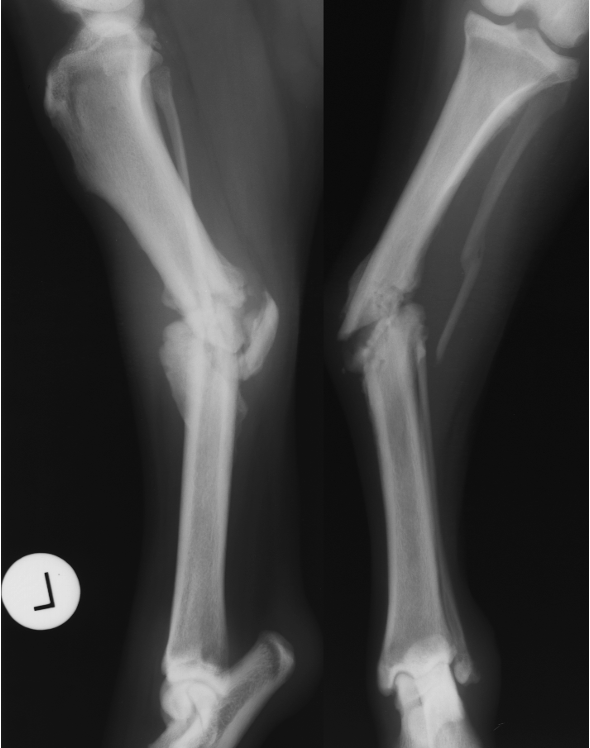

premature distal ulnar physis closure roentgen signs

gap - ulna and humerus, and gap at the bottom of ulna and carpus

cranial bowing of radius

premature distal radius physis closure roentgen signs

gap - radius and humerus, radius and carpus

no real ALD

which physis closed early

ulna

radius